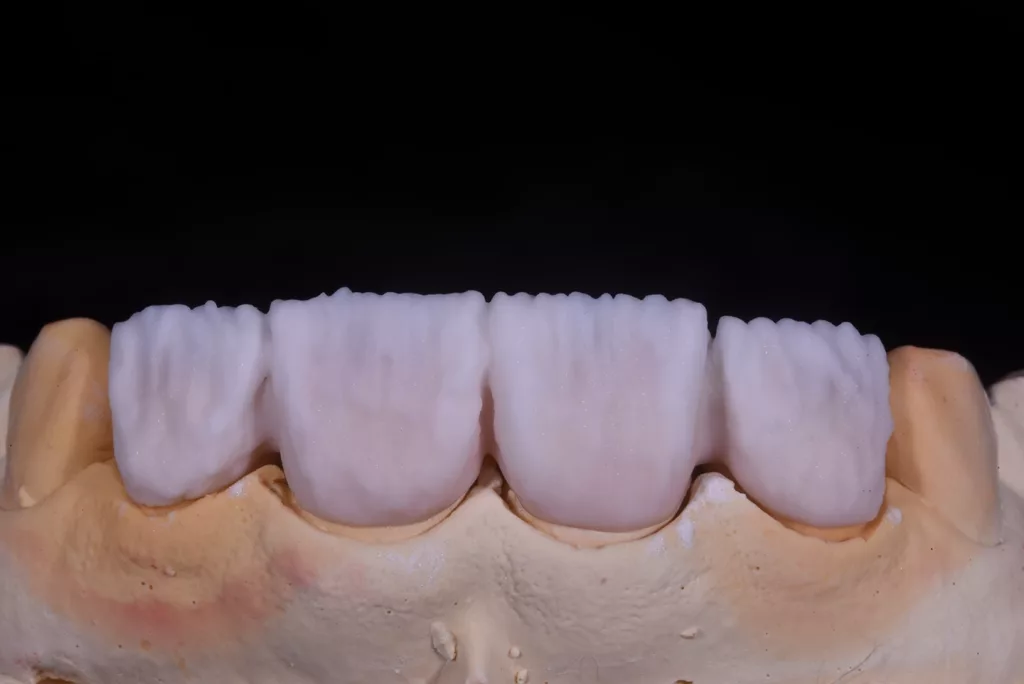

Die Kronen wurden in diesem Fall aus dem Material IPS e.max® ZirCAD Prime Esthetic von Ivoclar angefertigt. Die Transparenz des gewählten Zirkoniumdioxids ermöglichte die Fertigung dünner Kronen von 0,5 mm und gleichzeitig eine präzise Farbreproduktion ohne dicke Schichtung. Das Stumpfdesign wurde so gewählt, dass das Zirkoniumdioxid bis zur Inzisalkante reichte, um Schneidekantenfrakturen zu vermeiden. Die Schichtung erfolgte durch Auftragen von IPS e.max® Ceram Dentin-Pulver (OE1, OE2 und T1) auf das Grundgerüst (Abb. 57 bis 63).